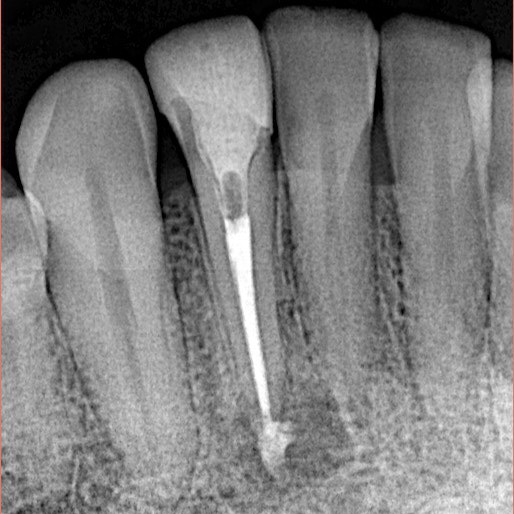

He Visited us because of pain in his fractured lower anterior tooth

Fractured Lower lateral incisor was necrotic and had periapical lesion as seen in X-ray